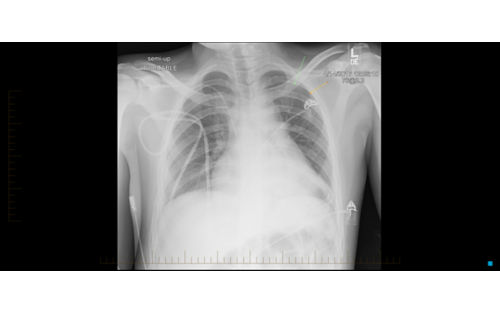

• Unexplained cough or shortness of breath